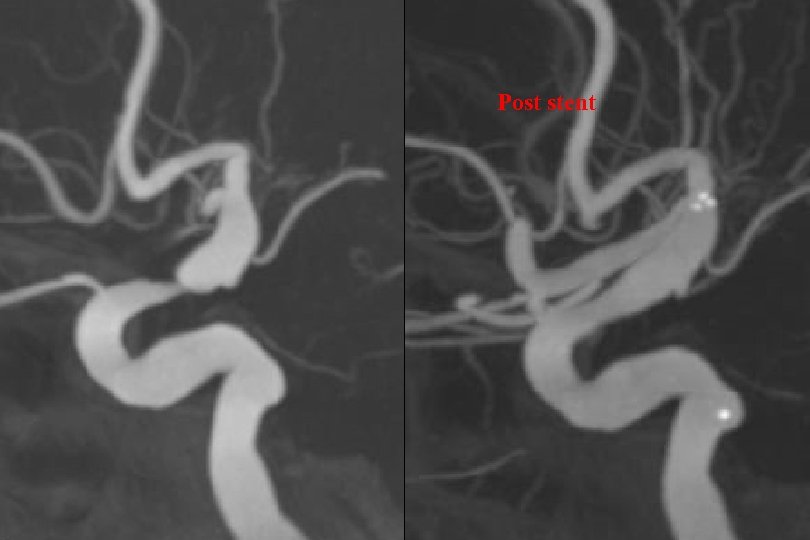

Post stent